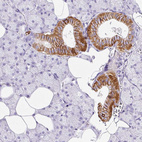

Immunohistochemistry analysis in human kidney and liver tissues using HPA053836 antibody. Corresponding BSND RNA-seq data are presented for the same tissues.